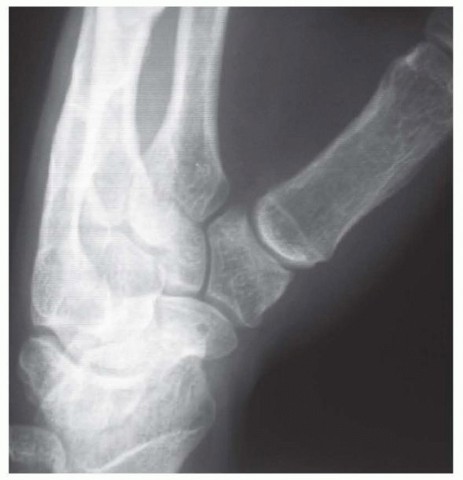

Our imaging protocol must be exhaustive to provide a three-dimensional understanding of the fracture morphology. Standard hand radiographs are insufficient due to the unique 30-degree pronated position of the thumb relative to the rest of the carpus. A True AP View of the Thumb CMC Joint (Robert's view) is obtained with maximal forearm pronation, placing the dorsum of the thumb flat on the cassette. This optimizes visualization of the joint space and the critical ulnar fragment. The True Lateral View (Billing and Gedda) is achieved with the hand pronated 20 degrees and the thumb flat on the cassette, with the X-ray beam tilted 10 degrees from vertical in a distal-to-proximal direction.

For complex, multi-fragmentary Rolando fractures, a Traction View under fluoroscopy is indispensable. Distraction at the CMC joint utilizes ligamentotaxis to help delineate comminuted fragments and assess the potential for closed reduction and percutaneous pinning versus the absolute need for open plating. Furthermore, when plain films inadequately delineate the spatial orientation of fracture fragments, particularly in Zone 2, a high-resolution Computed Tomography (CT) scan is strictly indicated. 3D reconstructions are invaluable for preoperative templating, allowing the surgeon to precisely map screw trajectories and select appropriate plate morphology before entering the operating theater.

Fixation Strategies for Rolando and Comminuted Patterns

Rolando fractures present a significantly higher degree of complexity. The classical Y or T pattern often precludes simple lag screw fixation. In these instances, mini-fragment plating is the gold standard. T-plates or specialized condylar plates are contoured to fit the complex geometry of the metacarpal base. The articular fragments are first reduced and provisionally pinned, essentially converting the complex intra-articular fracture into a simpler two-part extra-articular fracture. The plate is then applied to buttress the articular fragments and bridge the metaphyseal comminution to the diaphysis.

In cases of severe, non-reconstructable articular comminution where internal fixation is impossible, joint-spanning external fixation combined with limited internal fixation (K-wires) is utilized. The external fixator relies on the principle of ligamentotaxis to restore length and align the articular fragments. Pins are placed in the trapezium (or radius) and the thumb metacarpal shaft, distracting the joint to allow for secondary bone healing while preventing collapse.